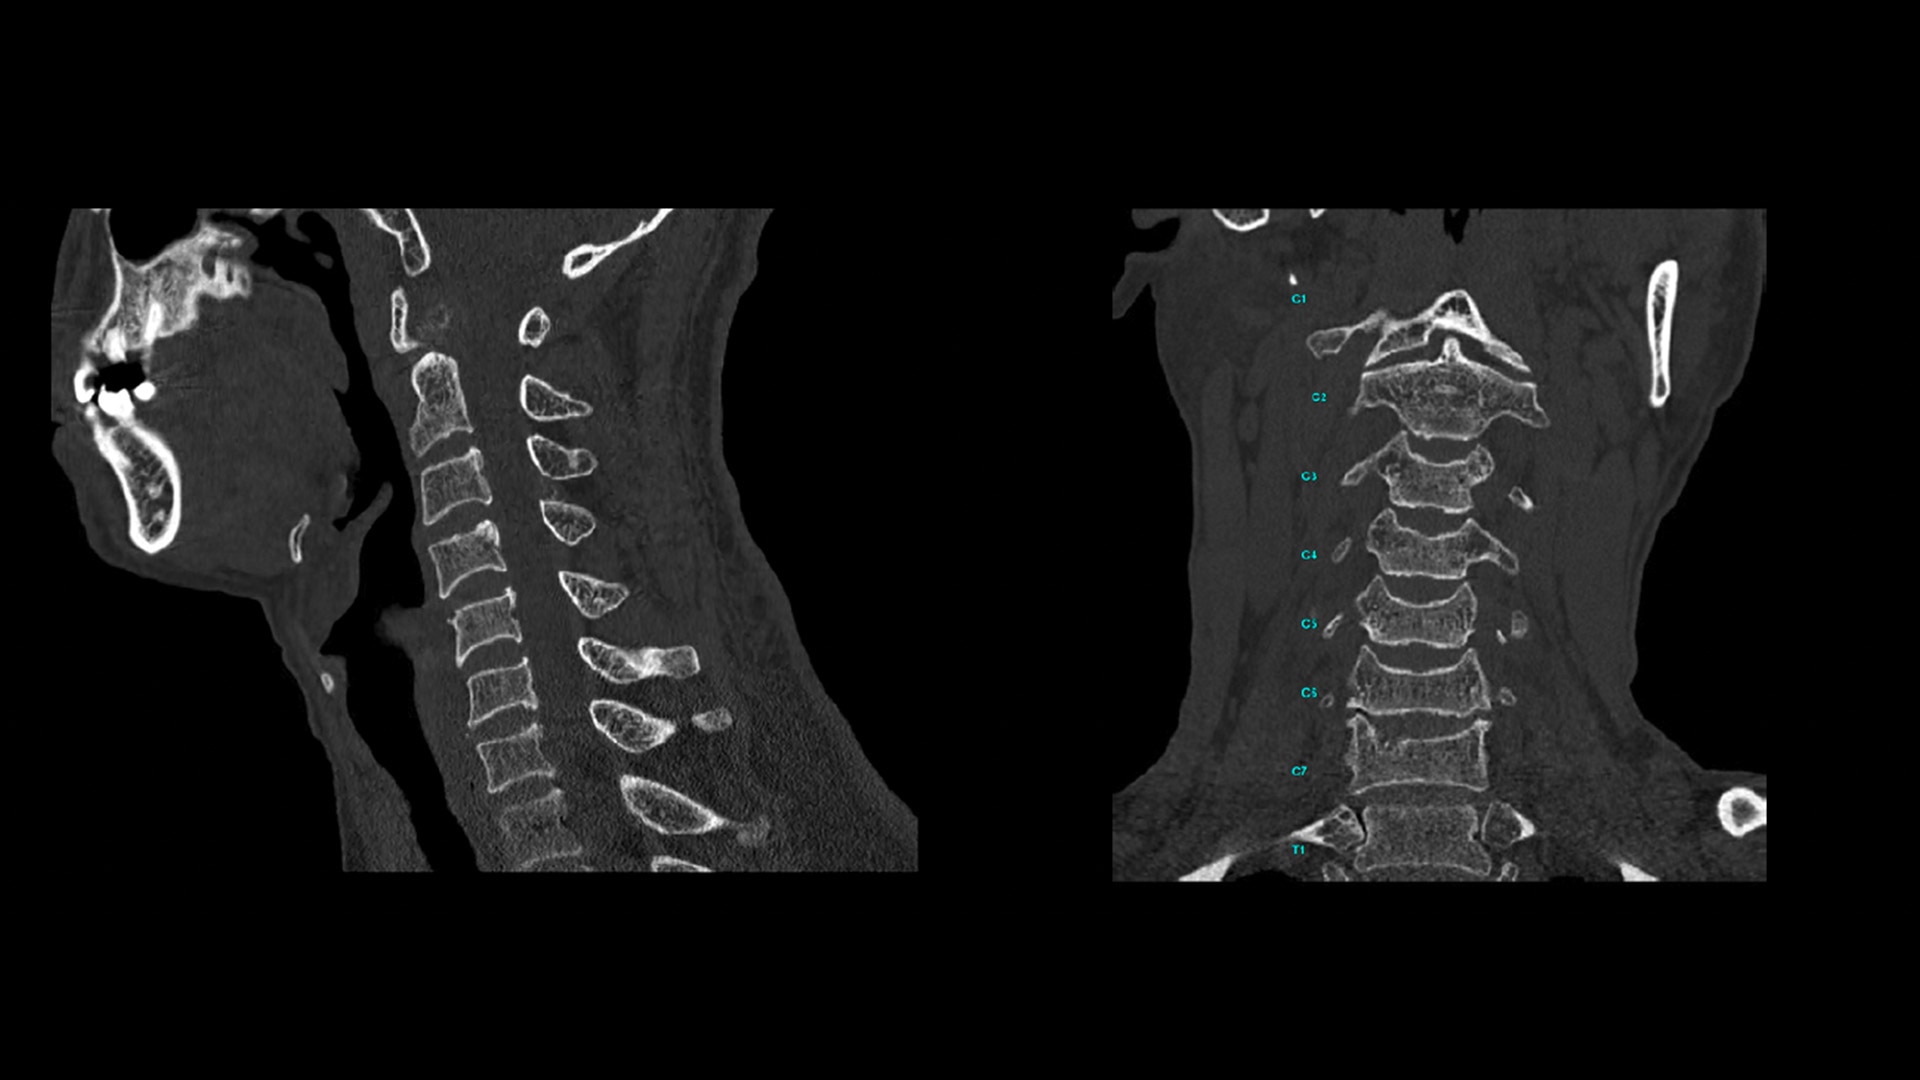

At the heart of Revolution Advance is a high-performance, reliable imaging chain with 42 kW of generator power, a 3.5 MHU X-ray tube and integrated detectors that reduce signal-to-noise by 20%2. This is paired with our smart, dose-reducing reconstruction applications like ASiR2, which can provide up to 40% lower dose while maintaining high image quality2.

When it comes to imaging more challenging cases, such as neuro, oncology or pediatric patients, VISR3. (Volumetric Image Space Reconstruction) reduces noise without impacting image resolution. This means less dose for the patient while maintaining the high-image quality you need for more accurate diagnoses.